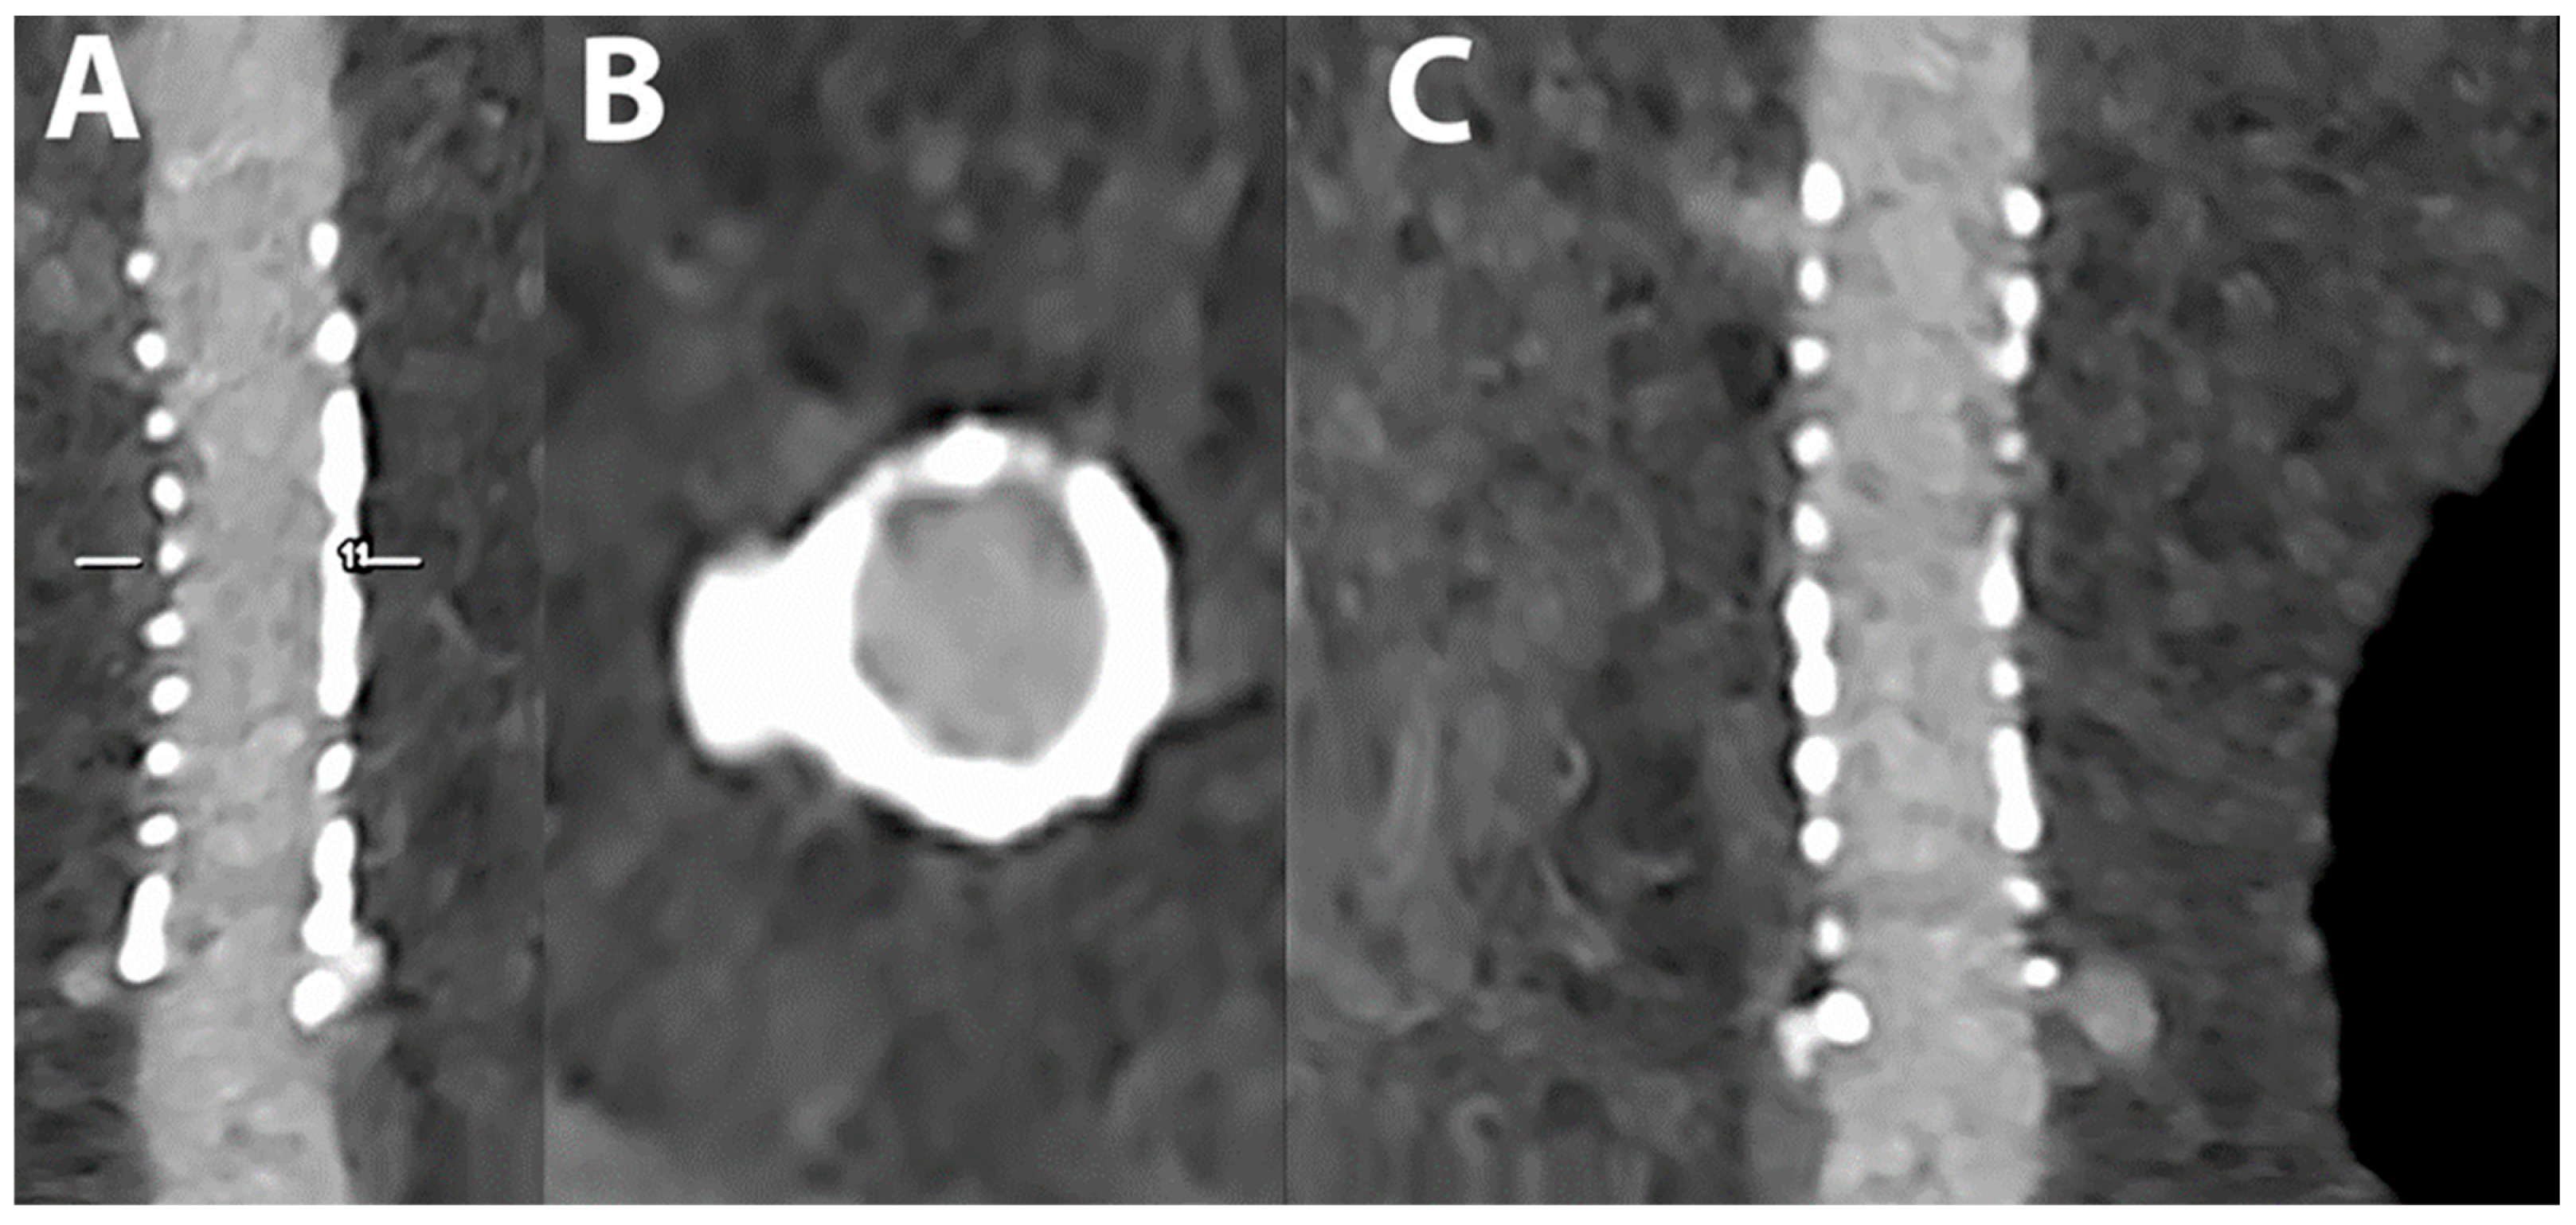

5.4. Coronary Artery Stenting

- Mannil, M.; Hickethier, T.; von Spiczak, J.; Baer, M.; Henning, A.; Hertel, M.; Schmidt, B.; Flohr, T.; Maintz, D.; Alkadhi, H. Photon-Counting CT: High-Resolution Imaging of Coronary Stents. Investig. Radiol. 2018, 53, 143–149. [Google Scholar] [CrossRef]

- Symons, R.; De Bruecker, Y.; Roosen, J.; Van Camp, L.; Cork, T.E.; Kappler, S.; Ulzheimer, S.; Sandfort, V.; Bluemke, D.A.; Pourmorteza, A. Quarter-millimeter spectral coronary stent imaging with photon-counting CT: Initial experience. J. Cardiovasc. Comput. Tomogr. 2018, 12, 509–515. [Google Scholar] [CrossRef] [PubMed]

- von Spiczak, J.; Mannil, M.; Peters, B.; Hickethier, T.; Baer, M.; Henning, A.; Schmidt, B.; Flohr, T.; Manka, R.; Maintz, D.; et al. Photon Counting Computed Tomography With Dedicated Sharp Convolution Kernels: Tapping the Potential of a New Technology for Stent Imaging. Investig. Radiol. 2018, 53, 486–494. [Google Scholar] [CrossRef] [PubMed]

- Rajagopal, J.R.; Farhadi, F.; Richards, T.; Nikpanah, M.; Sahbaee, P.; Shanbhag, S.M.; Bandettini, W.P.; Saboury, B.; Malayeri, A.A.; Pritchard, W.F.; et al. Evaluation of Coronary Plaques and Stents with Conventional and Photon-counting CT: Benefits of High-Resolution Photon-counting CT. Radiol. Cardiothorac. Imaging 2021, 3, e210102. [Google Scholar] [CrossRef] [PubMed]

- Boccalini, S.; Si-Mohamed, S.A.; Lacombe, H.; Diaw, A.; Varasteh, M.; Rodesch, P.A.; Villien, M.; Sigovan, M.; Dessouky, R.; Coulon, P.; et al. First In-Human Results of Computed Tomography Angiography for Coronary Stent Assessment With a Spectral Photon Counting Computed Tomography. Investig. Radiol. 2022, 57, 212–221. [Google Scholar] [CrossRef] [PubMed]

- Bratke, G.; Hickethier, T.; Bar-Ness, D.; Bunck, A.C.; Maintz, D.; Pahn, G.; Coulon, P.; Si-Mohamed, S.; Douek, P.; Sigovan, M. Spectral Photon-Counting Computed Tomography for Coronary Stent Imaging: Evaluation of the Potential Clinical Impact for the Delineation of In-Stent Restenosis. Investig. Radiol. 2020, 55, 61–67. [Google Scholar] [CrossRef] [PubMed]